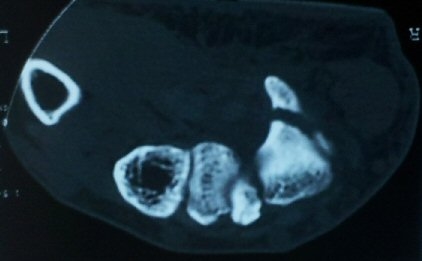

¼ÒÁö±¸ ³»Ãø¿¡ ȾÀ¸·Î ŽÃËÀÚ¸¦ ´ë¾î °¥°í¸®»À °¥°í¸® ³»Ãø¸é ÇÇÁú°ñÀ» °üÂûÇÏ´Ï(¾Æ·¡ ±×¸²)

°¥°í¸® ÇÇÁú°ñ ¿¬¼Ó¼º ¼Ò½Ç(loss of cortical continuity of hook of hamate)ÀÌ °üÂûµÈ´Ù(±×¸² 1, 2).

ÇÇÁú°ñ ¿¬¼Ó¼º ¼Ò½ÇÀº °ÇÃø°ú ºñ±³ÇØ¸é ´õ¿í ¶Ñ·ÈÇÏ´Ù(±×¸² 3, 4).